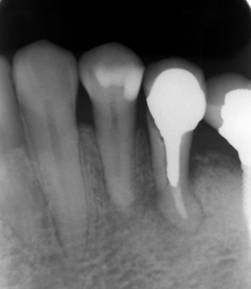

術後のCBCT

インプラントの重大な事故は下顎管から十分な距離をとれば防げます

インプラントにする前のパノラマレントゲン

抜歯部位にインプラントを追加しました。CBCT